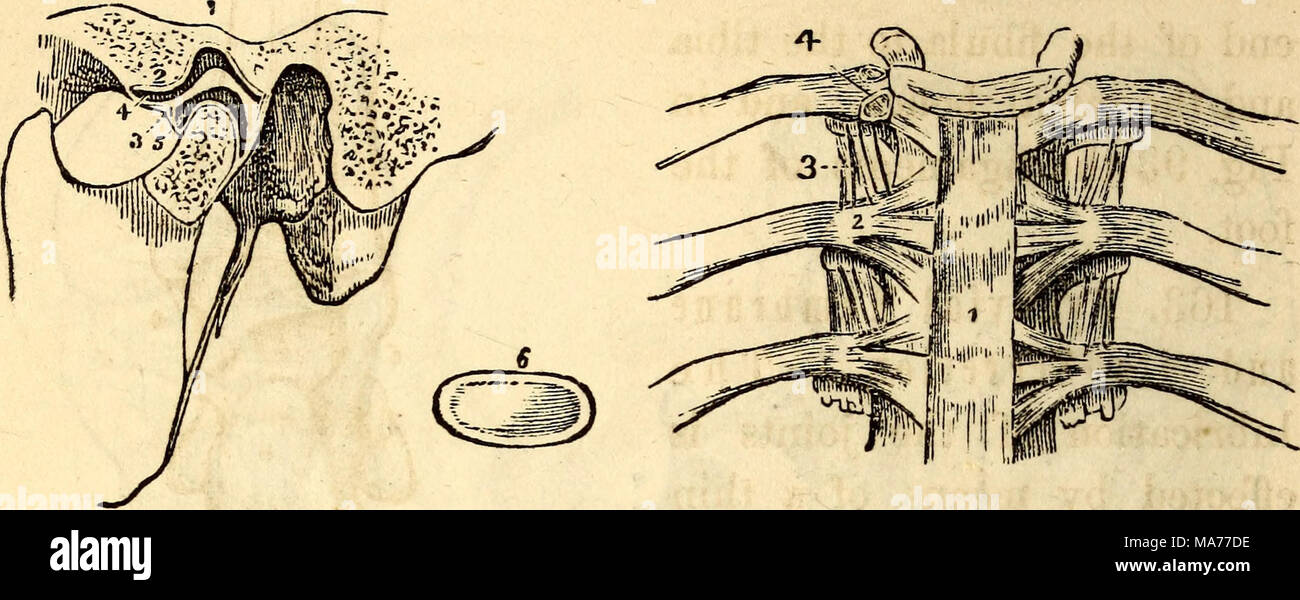

RMMA77DE–. Elementari di anatomia e fisiologia : Per college, accademie e altre scuole . Una vista anteriore dei legamenti delle vertebre e delle costole. 1, la sezione anteriore del legamento vertebrale. 2, il costo anteriore- legamento vertebrale. 3, l'interno legamento trasversale. 4, il Inter-Ar- o sovracapacità per particolari legamento, colleganti la testa della costola al sub intervertebrale- posizione. Una vista dell'articolazione della mandibola, dato dalla segatura attraverso il giunto. 1, la Fossa glenoide. 2, il tubercolo per condilo nel suo avanzamento- zioni. 3, la cartilagine Inter-Articular. 4, il superiore della cavità sinoviali. 5, il file INF